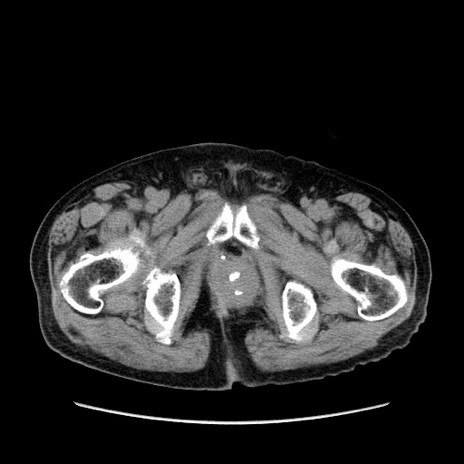

症例24(横断像)

【症例】80歳代男性

【主訴】左側腹部痛、嘔吐

【現病歴】本日早朝より左腹部に痛みあり。昼頃嘔吐認めたため、救急要請。

【既往歴】直腸癌(Mile手術)、胆摘

【身体所見】意識清明、BT 35.9℃、BP 221/93mmHg、SpO2 97%(RA) 、腹部:左ストーマ周囲に限局性の腹部膨隆あり。 膨隆部自発痛・圧痛あり・軟。

【データ】WBC 7700、CRP 0.09